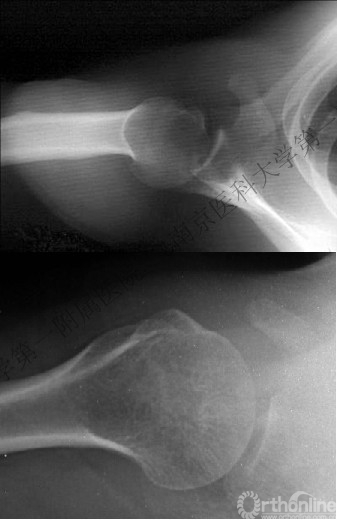

五、反Hill-Sachs 损伤对肩关节稳定性的影响

1.反Hill-Sachs损伤范围对肩关节后方稳定性具有决定性的影响。

2.常规的影像学测量方法不能准确反映损伤范围。

(五)修复反Hill-Sachs损伤

1.外旋肱骨头,显露肱骨头关节面损伤处。

2.改良McLaughlin术、 Underpinning术、球囊扩张术。

3.Dubousset 方法:对肱骨头关节面压缩性骨折均给予直视下复位、填充植骨、螺钉固定,手术指征不受压缩部分占总关节面面积比例的限制。